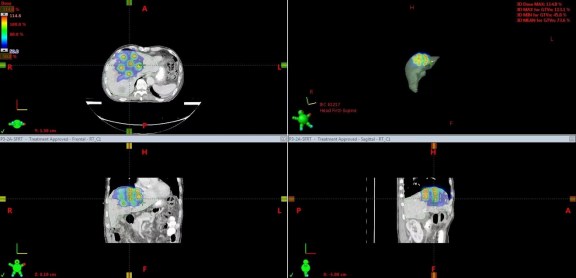

本次治疗的患者是一位结肠癌术后、靶向及化疗后出现肝转移的病人。针对其病情,选择了每次600cGy,总共五次的SFRT治疗方案,并同步应用了免疫疗法(PD-1抑制剂)。这种联合疗法不仅能精准打击肿瘤细胞,同时激活患者的免疫系统,进一步抑制肿瘤扩散。

在治疗过程中,使用TrueBeam平台的精密计划系统,确保了每一剂量都能够精准作用于肿瘤病灶,同时最大限度地减少了对正常肝脏组织的损伤。从治疗计划到实施,整个流程保持高水平的精度和稳定性。